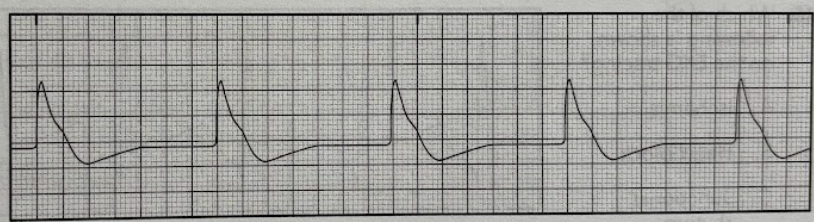

Using the 6-second method, determine the patient’s heart rate from the EKG tracing.

A. 80/min

B. 90/min

C. 190/min

D. 210/min

C